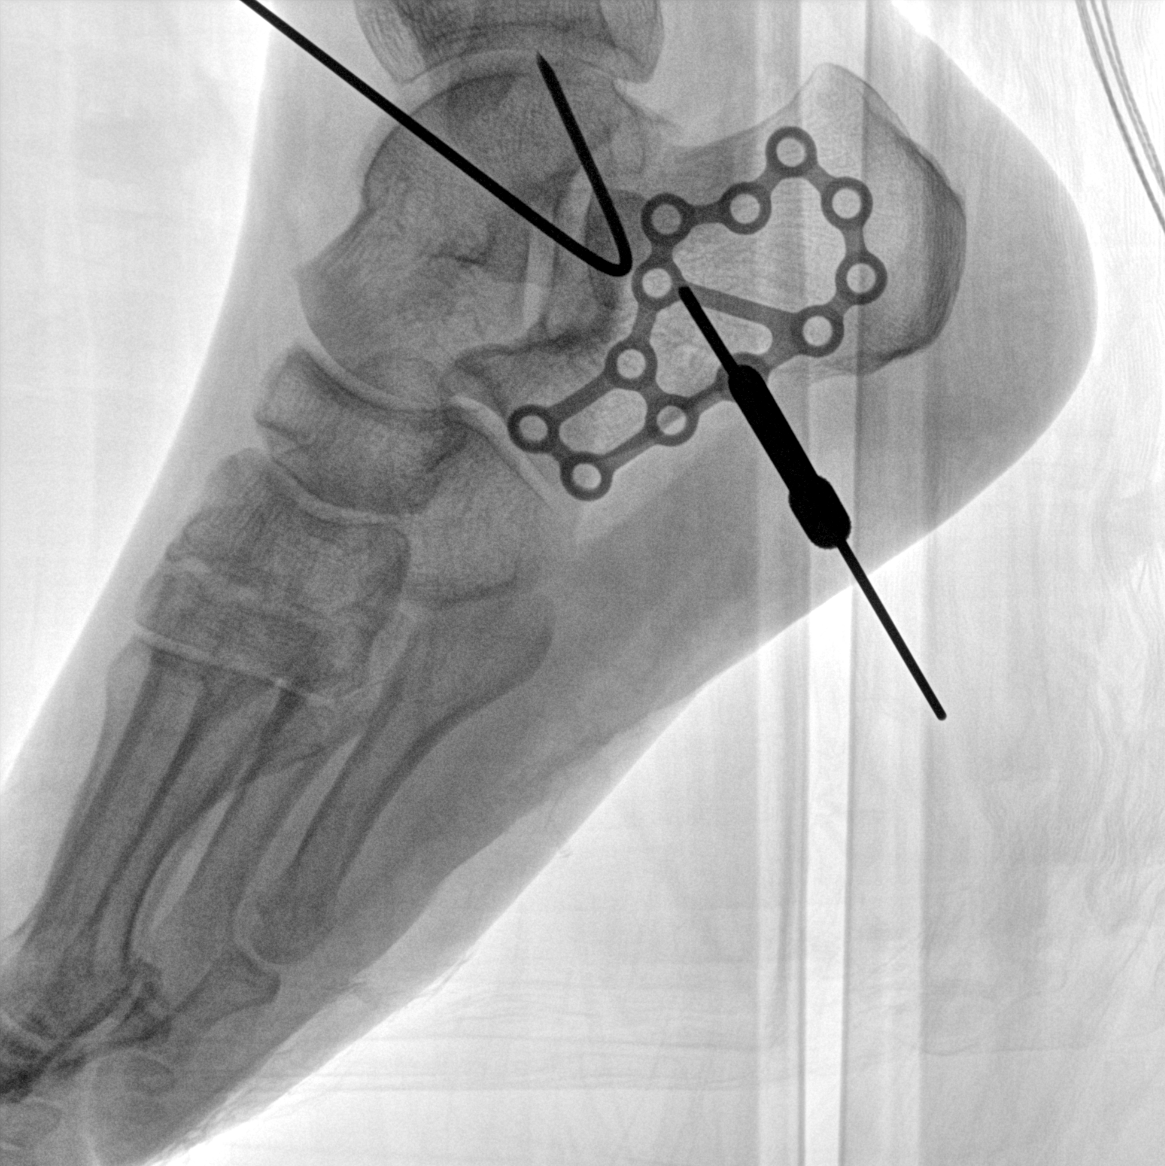

術(shù)中三維成像和橫斷面圖像提供多角度的手術(shù)診斷信息,輔助醫(yī)生進(jìn)行術(shù)中評(píng)估判斷,諸如骨折復(fù)位情況和內(nèi)植入螺釘?shù)某叽绾臀恢茫o助手術(shù)更好地完成。